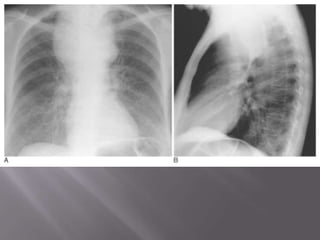

 Thymic cyst producing an anterior mediastinal mass on (A) AP and (B) lateral chest

radiographs, filling in the normal retrosternal window and widening the mediastinum.

 Thymic cystproducing an anterior mediastinal mass on (A) AP and (B) lateral chest radiographs, filling in the normal retrosternal window and widening the mediastinum. (C) The cystic nature is best demonstrated by CT.